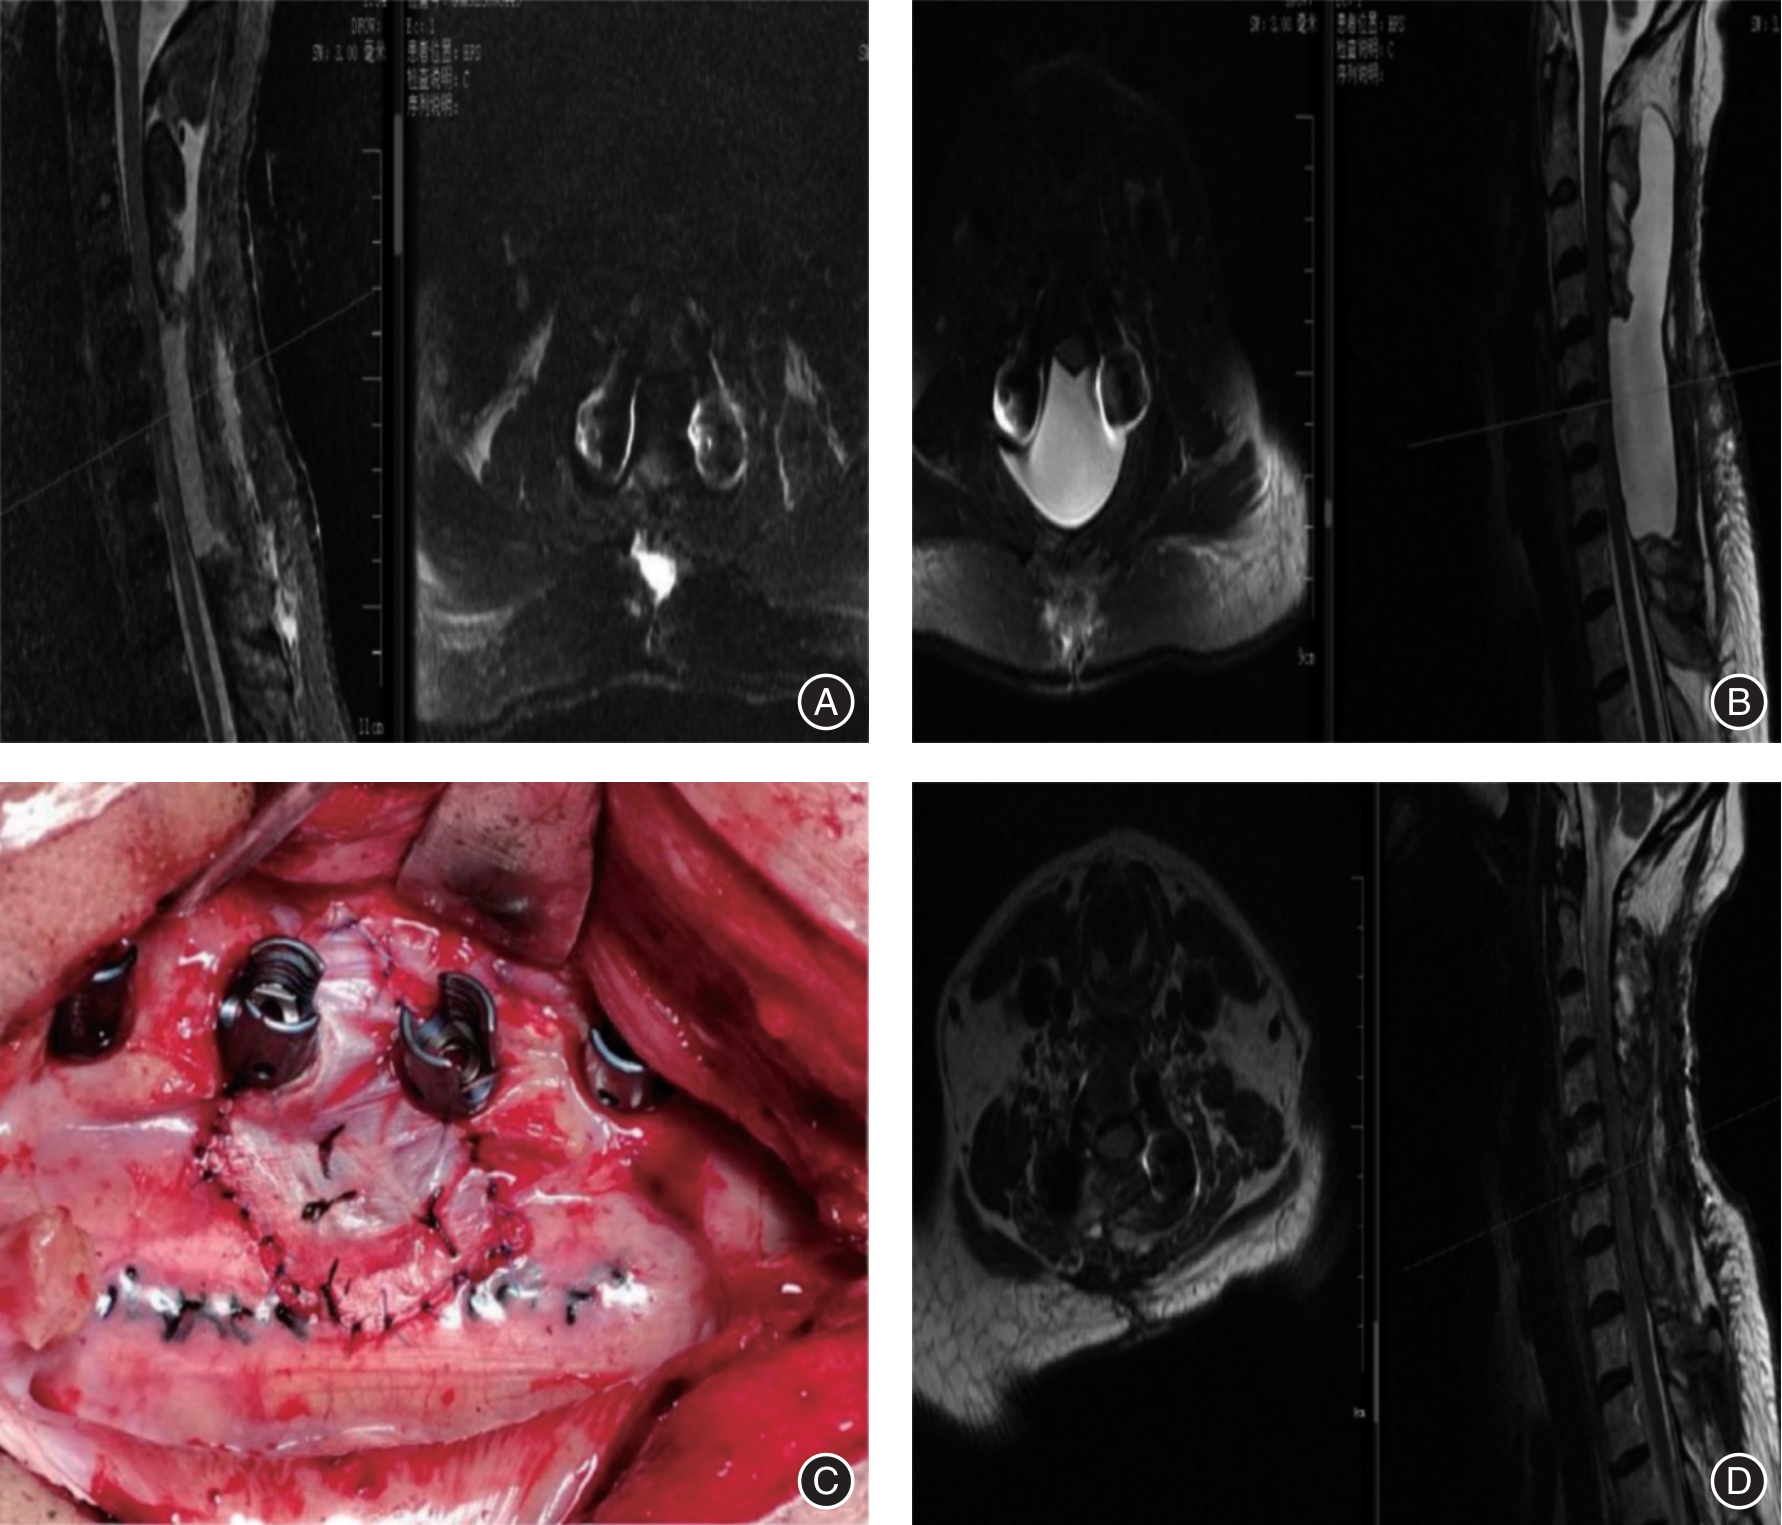

目的 研究用于辅助椎管内肿瘤切除手术的3D显微镜技术对椎管内肿瘤疾病的临床治疗效果与安全性。 方法 分析2019年1月至2023年7月治疗的椎管内肿瘤患者37例,采用3D显微镜下肿瘤切除(3D组)治疗的患者15例,采用普通显微镜下肿瘤切除(普通组)治疗的患者22例。比较两组患者的围术期指标、临床疗效指标、安全性指标。 结果 普通组手术时间(223.78 ± 46.46)min,3D组手术时间(182.93 ± 39.28)min,与普通组相比手术时间明显偏低(P < 0.05),其他围手术期指标两组比较差异无统计学意义(P > 0.05)。所有患者在术后疼痛症状均得到明显减轻,并且在一定程度上恢复了较好神经功能。对比术前,两组患者术后24 h以及术后1年的VAS评分,差异有统计学意义(P < 0.01),组间比较差异无统计学意义(P > 0.05), McCormick脊髓功能评级在术后1年均为Ⅰ级。两组术后并发症发生率差异无统计学意义。 结论 使用3D显微镜技术与普通显微镜技术进行椎管内肿瘤手术均具有较好的临床疗效。但于3D显微镜下能明显缩短手术时间,以此降低手术并发症的风险,具有更优的临床安全性。

Objective To investigate the clinical treatment effect and safety of 3D microscopy technology for adjuvant neuraxial tumor resection on neuraxial tumor diseases. Methods A total of 37 patients with neuraxial tumors treated from January 2019 to July 2023, 15 patients treated with 3D microscope tumor resection (3D group), and 22 patients treated with general microscope tumor resection (ordinary group) were analyzed. The perioperative indexes, clinical efficacy indexes and safety indexes were compared between the two groups. Results The operation time was (223.78 ± 46.46) min in the ordinary group and (182.93 ± 39.28) min in the 3D group, which was significantly lower than that in the ordinary group (P < 0.05), and there was no significant difference in other perioperative indicators between the two groups (P > 0.05). All patients had significantly reduced their postoperative pain symptoms and recovered their neurological function to a certain extent. There were statistically significant differences between the two groups (P < 0.01), but there was no statistical difference between the two groups (P > 0.05), and the McCormick spinal cord function rating was grade I. at one year after surgery. Conclusion The use of 3D microscopy and general microscopy for neuraxial tumor surgery has good clinical efficacy. However, the operation time can be significantly shortened under 3D microscopy, thereby reducing the risk of surgical complications and has better clinical safety.